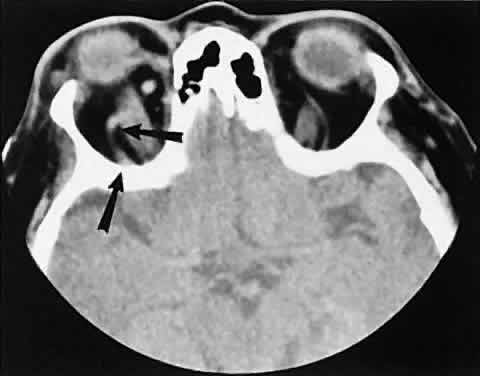

Low-flow lesions result from increased blood flow through the cavernous sinus, but the intracavernous carotid artery itself is intact (Fig. 3). These typically are dural-cavernous sinus fistulas. A high index of suspicion may be required to diagnose these, but a fairly stereotyped presentation is a unilateral red-eyed glaucoma with proptosis. Abduction weakness also may be present. Enlargement of one or more EOMs along with an enlarged SOV are noted with CT scanning. A small lesion may escape detection with CT scanning and require high-resolution MRI or even selective internal and external carotid angiography for diagnosis if a high degree of clinical suspicion exists. In a patient with a known dural fistula, a sudden and dramatic deterioration in the clinical picture may be seen with a thrombosis of the SOV.11 The radiographic picture, at least regarding the CT appearance, probably will not change. MRI can nicely show the thrombosis in the SOV.

Fig. 3. Axial view showing a dilated superior ophthalmic vein (SOV; arrows) secondary to dural-cavernous sinus fistula. Note the normal-sized SOV in the contralateral orbit.